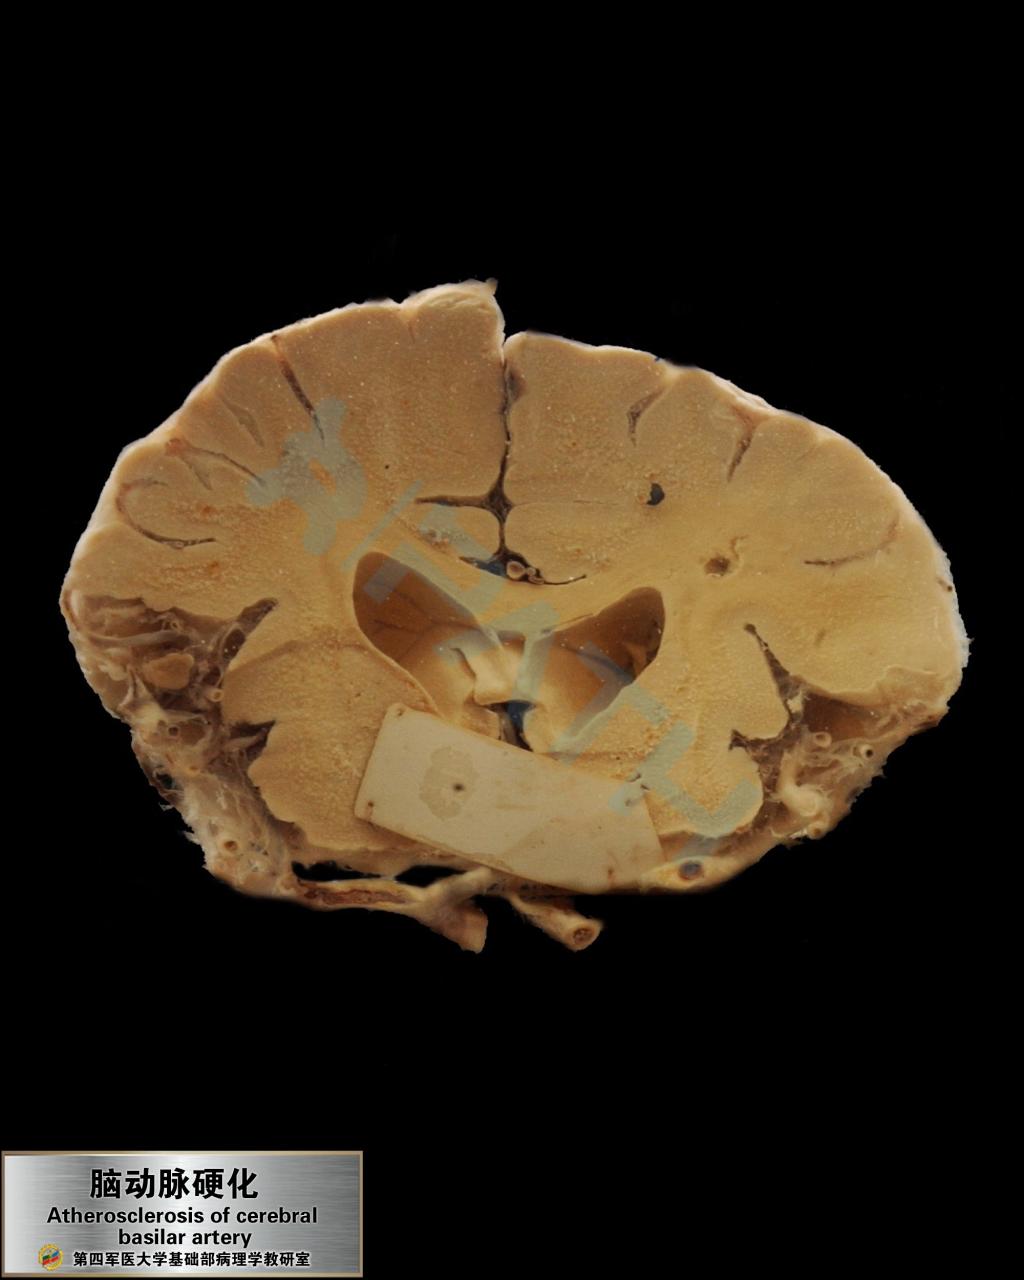

脑动脉粥样硬化